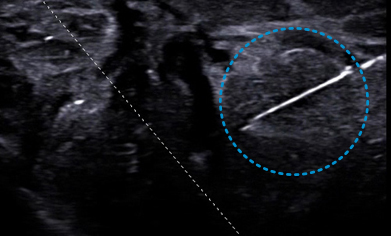

NeedleMate™

Needle Mate™ ensures precise needle targeting when performing operations such as a nerve block. Beam steering improves the accuracy and efficiency of diagnosis.